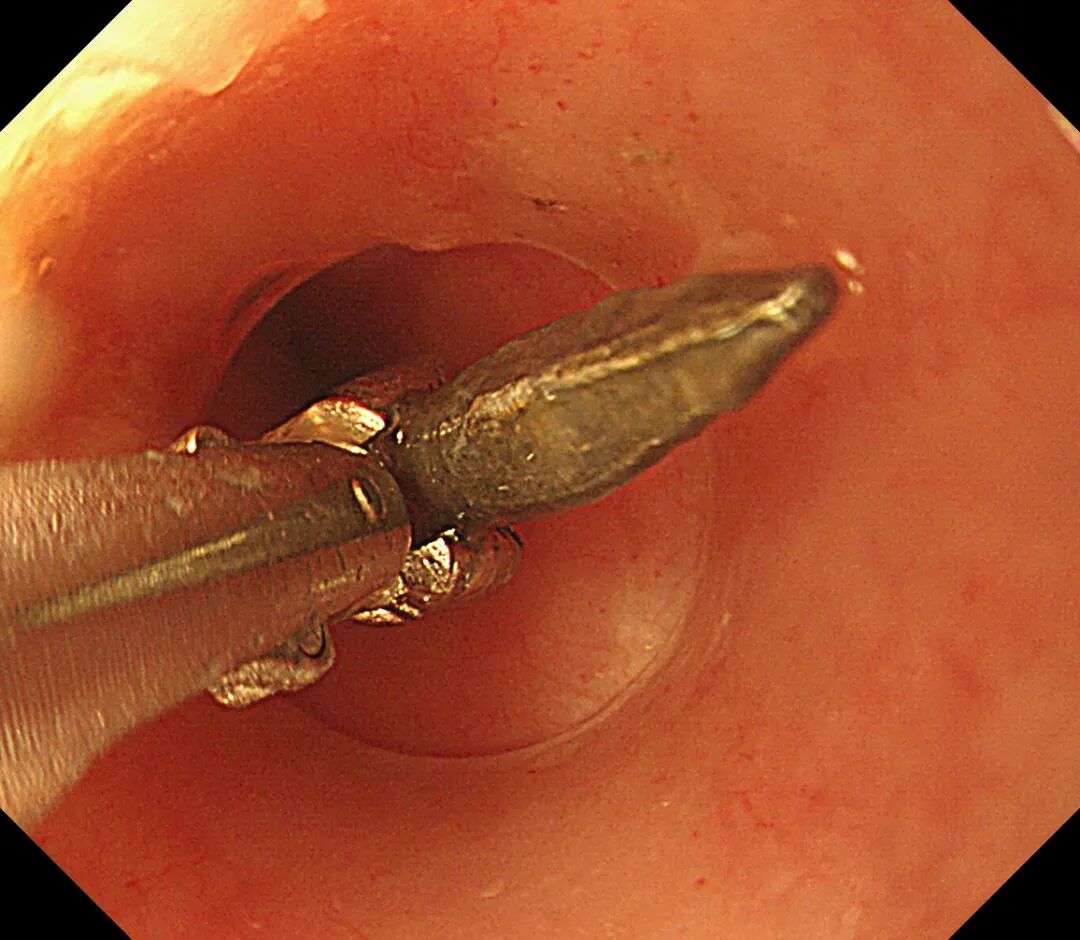

如何安全成功地夹取铁钉,是摆在颜主任面前的第一大难题,她立即换用能一次性抓取到更多异物的圈套器,小心翼翼地将5枚铁钉一并圈住,这时在场的医务人员顿时松了一口气。

圈套器将十二指肠降段的铁钉套住

但是如何将5枚4公分长的铁钉通过近乎直角的十二指肠球降交界转角处,以及再从狭小的幽门口取出,成了又一大难题,面对不断出现的困难,颜主任凭借多年的内镜经验,及时调整圈套器夹取铁钉的距离和方向,改变铁钉与腔道的角度,顺利将5枚铁钉拉到胃内,并将其全部取出体外,为确保患儿体内已无铁钉,急诊行床旁腹部摄片检查,结果提示患儿腹部未查见高密度金属影,宣告所有铁钉已全部取出,顿时整个手术室一片欢呼。